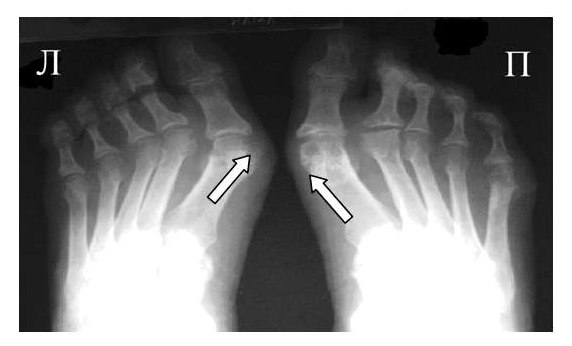

Одним из главных отличительных признаков ревматоидного артрита (РА) от других заболеваний является симметричность изменений мелких суставах кистей и стоп, которые становятся суставами-«мишенями» в первую очередь и поэтому именно эти области изучаются для определения стадии заболевания. Наиболее часто используемой в повседневной практике рентгенологической классификацией является деление ревматоидного артрита на стадии по Steinbrocker в различных модификациях.

Основные симптомы

Основными рентгенологическими симптомами РА являются следующие: остеопороз, кистовидные просветления костной ткани (кисты), сужение суставной щели, эрозии суставов, костные анкилозы, деформации костей, остеолиз, вывихи, подвывихи и сгибательные контрактуры суставов. Рентгенологическая диагностика развернутых стадий РА, исходя из нашей практики, как правило, затруднений не вызывают.

Большинство ошибок встречаются при начальных стадиях, особенно при начале РА в пожилом возрасте и сочетании его с остеоартрозом (см. рис. 3). В этом случае для подтверждения диагноза РА и предупреждению случаев его гипердиагностики служит выявление симметричных эрозий в типичных для ревматоидного артрита суставах (запястья, плюснефаланговые, пястно-фаланговые).

Рис. 4. Изменения кистей при ревматоидном артрите (а остеопороз, бсужение суставных щелей, в кистовидные просветвления, г костные эрозии, д анкилозирование)

Необходимо также помнить, что, как правило, при РА эрозии не предшествуют околосуставному остеопорозу, кистам и сужению суставных щелей. Имеет место последовательность развития стадий РА (см. рис. 4), в отличие от эрозивных артритов другого генеза (псориатического, серонегативного)

Костные анкилозы выявляются только в суставах запястий и во 2-5-м запястно-пястном суставах, редко в лучезапястных и суставах предплюсны. Никогда анкилозы не формируются в межфаланговых суставах кистей и стоп, в первых запястно-пястных и плюснефаланговых суставах. Анализируя сроки появления основных рентгенологических проявлений наиболее типичным по нашим данным и по данным других авторов [LandeweR.] является появление первых симптомов РА (околосуставного остеопороза и кистовидных просветлений) через несколько месяцев (до года) от начала заболевания, эрозии выявляют на 2-3 год от начала заболевания.